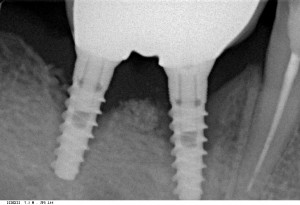

Например, установили имплантат, он успешно интегрировался. Ортопед сделал на такой имплант коронку. И все бы хорошо, но доктор-имплантолог проигнорировал остеопластику и восстановление объема кератинизированной десны, в результате имплантат оказался не там, где нужно, и не того размера, какой необходим для протезирования данного зуба. В результате, несмотря на старания ортопеда, выглядит такая конструкция просто ужасно, а пациент постоянно испытывает неудобства с гигиеной. Понятное дело, что из-за плохой гигиены развитие периимплантита почти неизбежно. Можно ли считать такую работу качественной? С точки зрения имплантолога — да. Ведь имплантат интегрировался, никаких проблем с окружающими имплант тканями нет. Пока нет. С точки зрения ортопеда — да. Ведь он сделал коронку, она стоит на импланте, сколов нет. А эстетика…. это же субъективное восприятие, кому-то нравится, а кому-то нет. Да и гигиена — индивидуальный навык, и доктора тут как бы совсем ни при чем. И, если это «качественно оказанная медицинская услуга» — что же пациент недоволен? Может быть, это просто капризный пациент? И таких, которые вечно и ко всем в претензии. Вряд ли….

импланты стоят, коронки на месте. Но можно ли считать такую работу качественной?